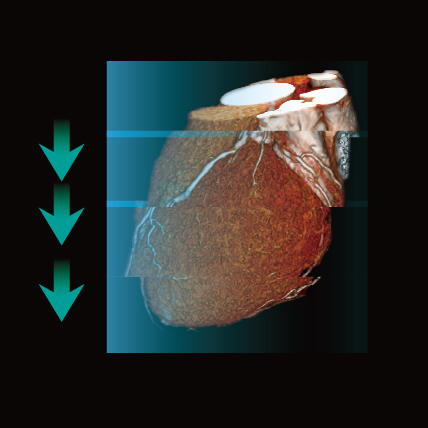

Assess the whole body in one scan

Variable Helical Pitch with three phases (vHP3)

Overall faster scan times make vHP3 compliant to the needs of the patient, and shorten exam times for trauma imaging when every second is critical.

A single series reconstruction enables several studies to be interpreted simultaneously for faster reading.